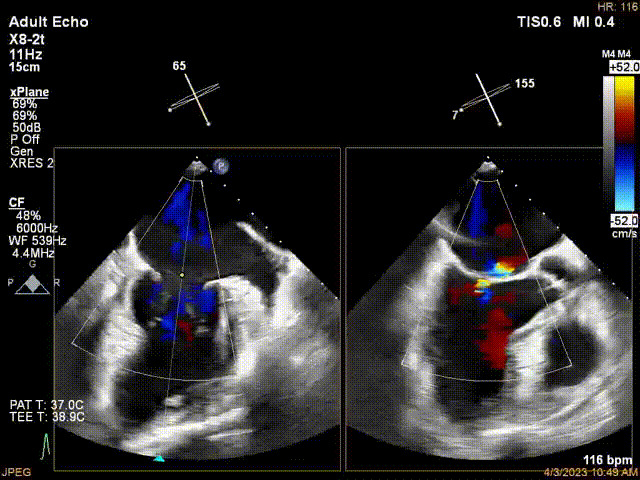

接受治療的是一例器質(zhì)性重度二尖瓣反流(DMR)患者,主訴“反復(fù)活動后胸悶,氣促3年余”。術(shù)前超聲顯示,雙房增大,二尖瓣脫垂伴重度反流,輕度三尖瓣反流,輕度肺高壓,升主動脈增寬。手術(shù)經(jīng)股靜脈-房間隔入路,采用全身麻醉插管,在TEE和DSA引導(dǎo)下完成房間隔穿刺。置入JensClip瓣膜夾系統(tǒng)后,在左房調(diào)整瓣膜夾的位置和軸向,后進(jìn)入左室,在TEE引導(dǎo)下捕捉二尖瓣前后瓣葉,并關(guān)閉瓣膜夾。經(jīng)TEE反復(fù)確認(rèn)手術(shù)效果后最終鎖定并釋放瓣膜夾。術(shù)后即刻超聲顯示瓣膜夾位置穩(wěn)定,功能良好,術(shù)前二尖瓣反流4+,術(shù)后0反流,肺靜脈逆流和左房壓都顯著好轉(zhuǎn),手術(shù)圓滿成功(以上數(shù)據(jù)都來源于醫(yī)院的臨床記錄)。術(shù)后患者狀態(tài)良好,目前已安排出院。

術(shù)后超聲顯示二尖瓣反流消失,瓣膜夾穩(wěn)定